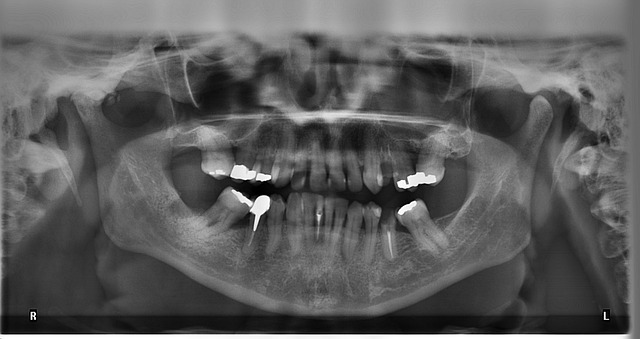

(2) 파노라마 엑스레이 (Panoramic X-ray)

입 전체를 한 장의 사진으로 촬영하는 방식입니다. 사랑니 상태를 확인하거나 교정 치료를 계획할 때 많이 활용됩니다. 한 번의 촬영으로 전체적인 치아 상태를 볼 수 있어 유용하지만, 부분 촬영보다 방사선 노출량이 다소 높을 수 있습니다.